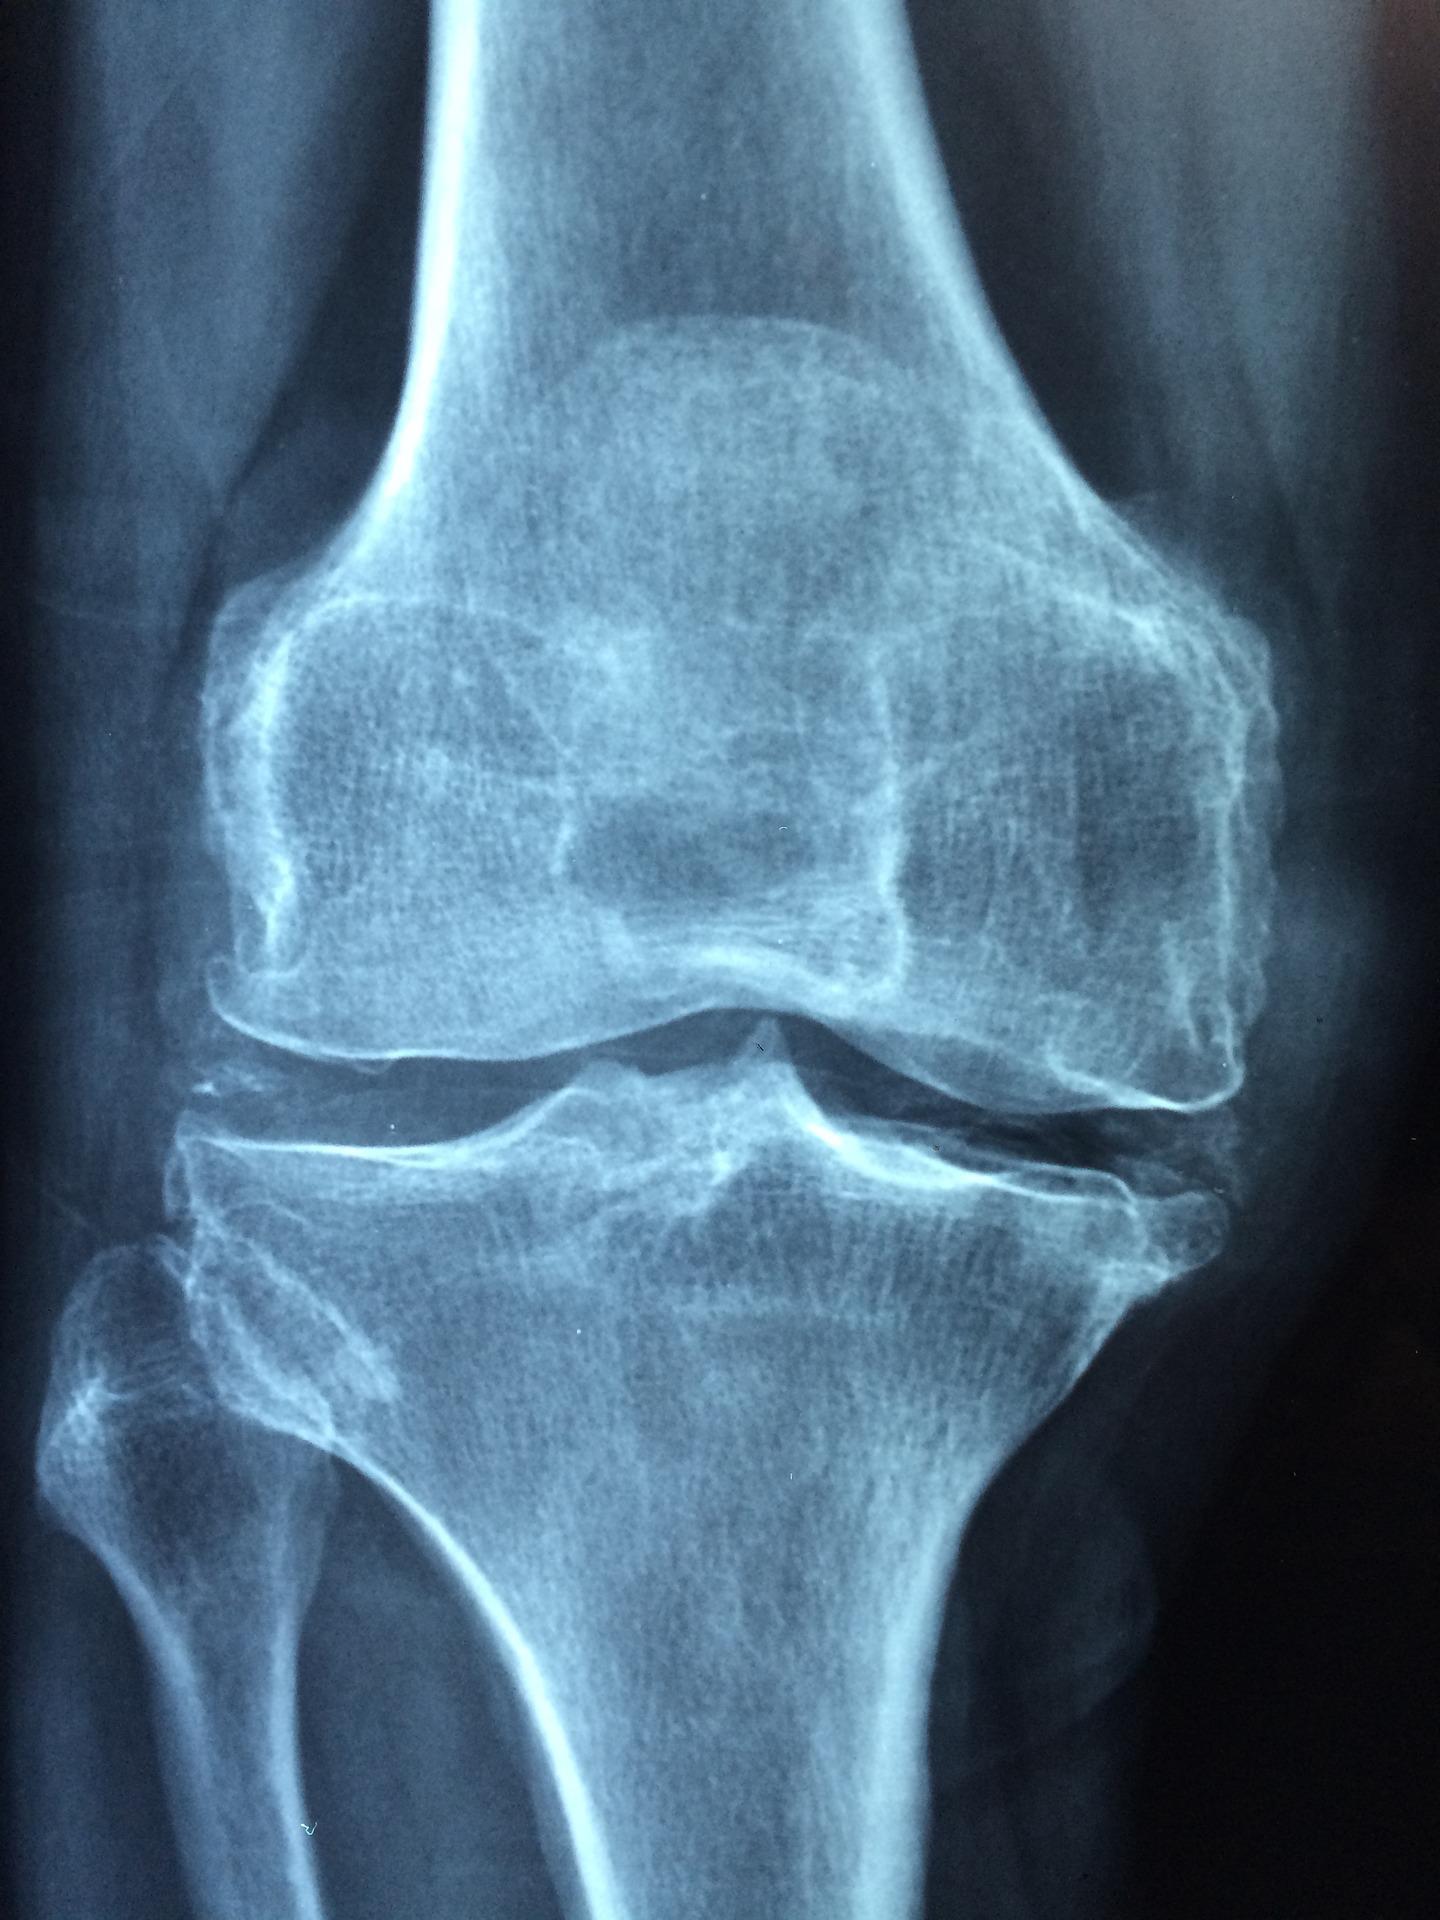

A osteopenia é uma redução da massa óssea que, quando não tratada, pode evoluir para osteoporose, que aumenta consideravelmente o risco de fraturas devido à fragilidade dos ossos. Segundo a médica radiologista, Angela Soares, exames de imagem são fundamentais para acompanhar a evolução da doença. “Por meio da densitometria óssea, é possível avaliar as chances de fraturas e checar a medida quantitativa da perda da massa óssea. A partir deste diagnóstico, o especialista vai definir o tratamento mais adequado para evitar que a doença evolua”, comenta.

Um levantamento realizado pela Fundação Instituto de Pesquisa e Estudo de Diagnóstico por Imagem (FIDI), gestora de serviços de diagnóstico por imagem na rede pública, aponta que, entre o segundo semestre de 2021 e o primeiro semestre de 2022, foram realizados cerca de 22 mil exames de densitometria óssea, o mais utilizado para diagnosticar osteoporose e osteopenia. Desses, 90% foram realizados em mulheres e apenas 10% em homens.